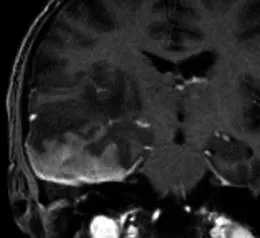

一名35歲頭痛女性的造影后冠狀T1加權(quán)序列顯示

一名35歲頭痛女性的造影后冠狀T1加權(quán)序列顯示,右中顱窩內(nèi)有均勻增強(qiáng)的軸外質(zhì)量,并有寬闊的硬腦膜尾(箭頭)沿著蝶骨翼延伸,并圍繞右額葉的側(cè)面。腫塊導(dǎo)致大腦鐮下向左突出7毫米,右側(cè)腦室消失。手術(shù)時(shí)的組織學(xué)結(jié)果為腦膜瘤(1級(jí))